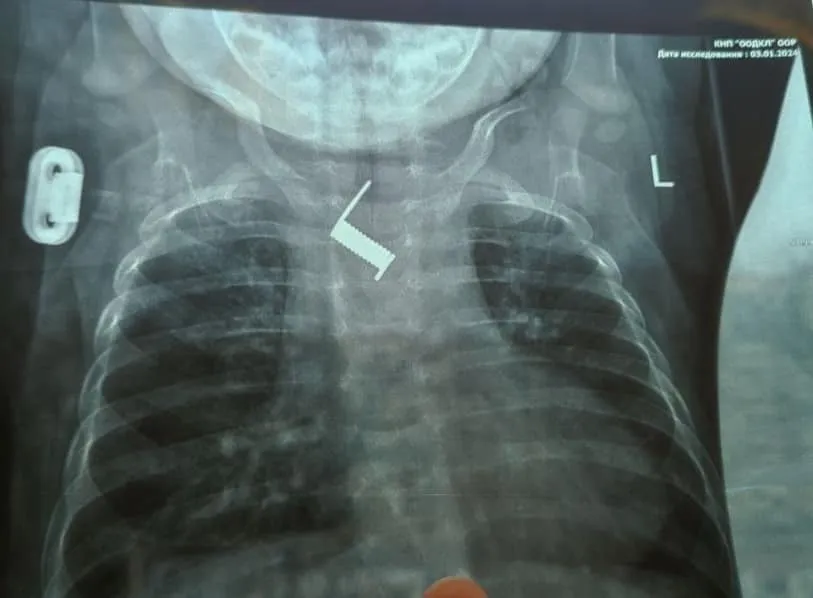

Медики зазначили, що за два тижні пружина майже вросла у стінку стравоходу немовляти. При потрапланні у стаціонар лікарні було виконано оглядову рентгенограму, за результатами якої було виявлено сторонній предмет у тілі дитини, а саме пружинку від шпильки для волосся.

"Знаходилось стороннє тіло на рівні середньої третини стравоходу, поряд з дугою аорти. Стороннє тіло було видалено ендоскопічно,що позбавило дитину від важкого хірургічного втручання та ризиків для життя", – розповіли медики.